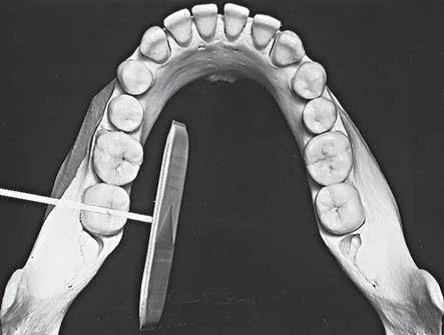

Hình 1. PHẠM VI ẢNH

Phim gồm có nửa xa của răng cối nhỏ thứ hai và ba răng cối lớn vĩnh viễn. Trong trường hợp răng cối lớn thứ ba mọc ngầm hoặc có tình trạng bệnh lý ở phía xa răng cối lớn thứ ba thì cần chụp thêm một phim vùng răng này hoặc phim ngoài miệng (phim panorex hoặc phim mặt nghiêng) để khảo sát đầy đủ hơn.

Hình 2. ĐẶT RECEPTOR

Đặt receptor số 2 vào miệng sao cho mặt phẳng của nó gần như nằm ngang. Xoay cạnh dưới của nó xuống dưới bờ lưỡi rồi dịch chuyển sao cho nó nằm vị trí ở giữa lưỡi và răng. Cạnh trước của receptor ngang với vị trí giữa răng cối nhỏ thứ hai. Trong hầu hết trường hợp, lưỡi sẽ đẩy receptor về phía xương ổ răng và răng, điều chỉnh để nó song song với trục chính của răng và mặt nhai răng.